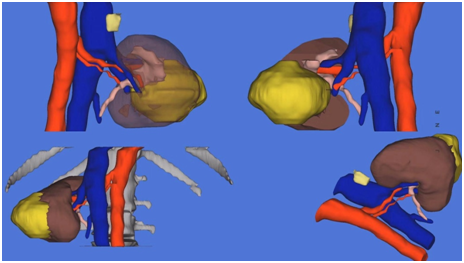

「東文教授非常重視術前規劃,此次他在深圳首次使用了原創專利技術——腹腔鏡腎臟手術個體化腎血管評價系統(SIREN 系統),通過手術前對患者的腎臟血管情況進行三維立體重建,不僅清晰顯示出了患者腎臟的動脈、靜脈血液供應情況,還可以預先對手術切除層面進行演示。」泌尿外科主任田軍教授說,藉助這項技術可對腎臟血管進行直觀、量化的評估,可以實現術前精細化的規劃,為複雜腎癌手術提供安全保障。